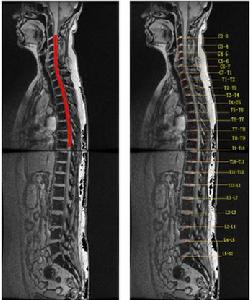

(2)間接外力交通事故,高處墜落及跳水意外時,外力多未直接作用於脊柱、脊髓,但間接外力可引起各種類型不同的脊柱骨折、脫位,導致脊髓損傷。間接外力作用是造成脊柱、脊髓損傷的主要原因。Gosolf等用猴進行多種活體脊柱損傷實驗,結論是要造成骨折脫位,除屈伸暴力外,必須要有軸向鏇轉暴力。而發生脊髓損傷的力的閾值,還受肌肉張力的重要影響。Gusta等報告46.3%的脊髓損傷患者是因剪力和扭力作用造成骨折脫位損傷脊髓,30.5%是因脊柱前中後三柱受壓損傷的結果,15.8%是因脊柱前中二柱受損結果,4.2%因過伸性脊柱損傷引起,而3.2%則是因外傷間盤突出引起脊髓損傷。近年來,人們注意到有些脊髓損傷並不伴有脊柱的骨折脫位,即外力的作用造成了脊髓損傷而沒有影象學可見的脊柱骨折脫位等異常發現。兒童的脊髓損傷多屬此種情況即SCIWORA。成人患者中有退化性脊椎病,椎管狹窄者也易發生,因易誤診應引起重視。MRI和電生理診查可為無骨折脫位的脊髓損傷提供一定診斷依據。了解外傷性脊髓損傷的具體原因,對採取相應措施預防或減少脊髓損傷的發生有重要意義。如高空作業安全帶的套用,汽車駕駛的安全帶的套用,嚴禁酒後開車以及最近汽車內防撞系統的套用等,均對脊髓損傷的預防有重要意義。